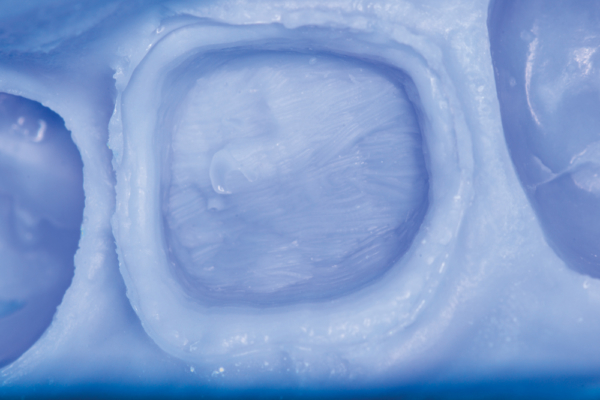

The quadrant impression tray must be wide enough, yet adaptable to fit a myriad of quadrant lengths, widths, and tooth position scenarios. As such, the adjusted tray has to be comfortable enough for the patient to endure the setting time. There can be no painful hard or soft tissue impingement that may alter the patient’s ability to occlude in the appropriate matter. The tray must also be stable throughout the impression procedure, regardless of the occlusal forces placed on it through the patient closing into the impression material, as well as during the removal of the impression from the mouth. Any distortion, no matter how slight, may result in an ill-fitting restoration requiring adjustments in order to be functional. The ideal tray will hold the tray material securely so that it does not pull away from the tray upon removal from the mouth. Tray stability throughout the impression procedure is paramount to a highly accurate final impression.

The tray material chosen for the dual-arch technique is also vital for providing the laboratory with a stable, accurate impression. Dual-arch impressions differ from full-arch impressions in that a great deal of dimensional stability of the impression depends on the rigidity or hardness of the tray material versus the metal or plastic full-arch tray. The best choice would be a tray material designed to be both as rigid as possible, yet displaying the ideal flow that does not displace the light body from the preparation. For optimal dimensional stability, ensure that the upper and lower aspects of the tray material are actually connected buccal and lingually.

The choice of light body is dependent on the particular syringing technique being used as well as its setting time. Furthermore, the setting time and the light body’s compatibility with the tray material is important to ensure a seamless interface between the two viscosities, as well as the light body’s ability to resist displacement by the tray material.